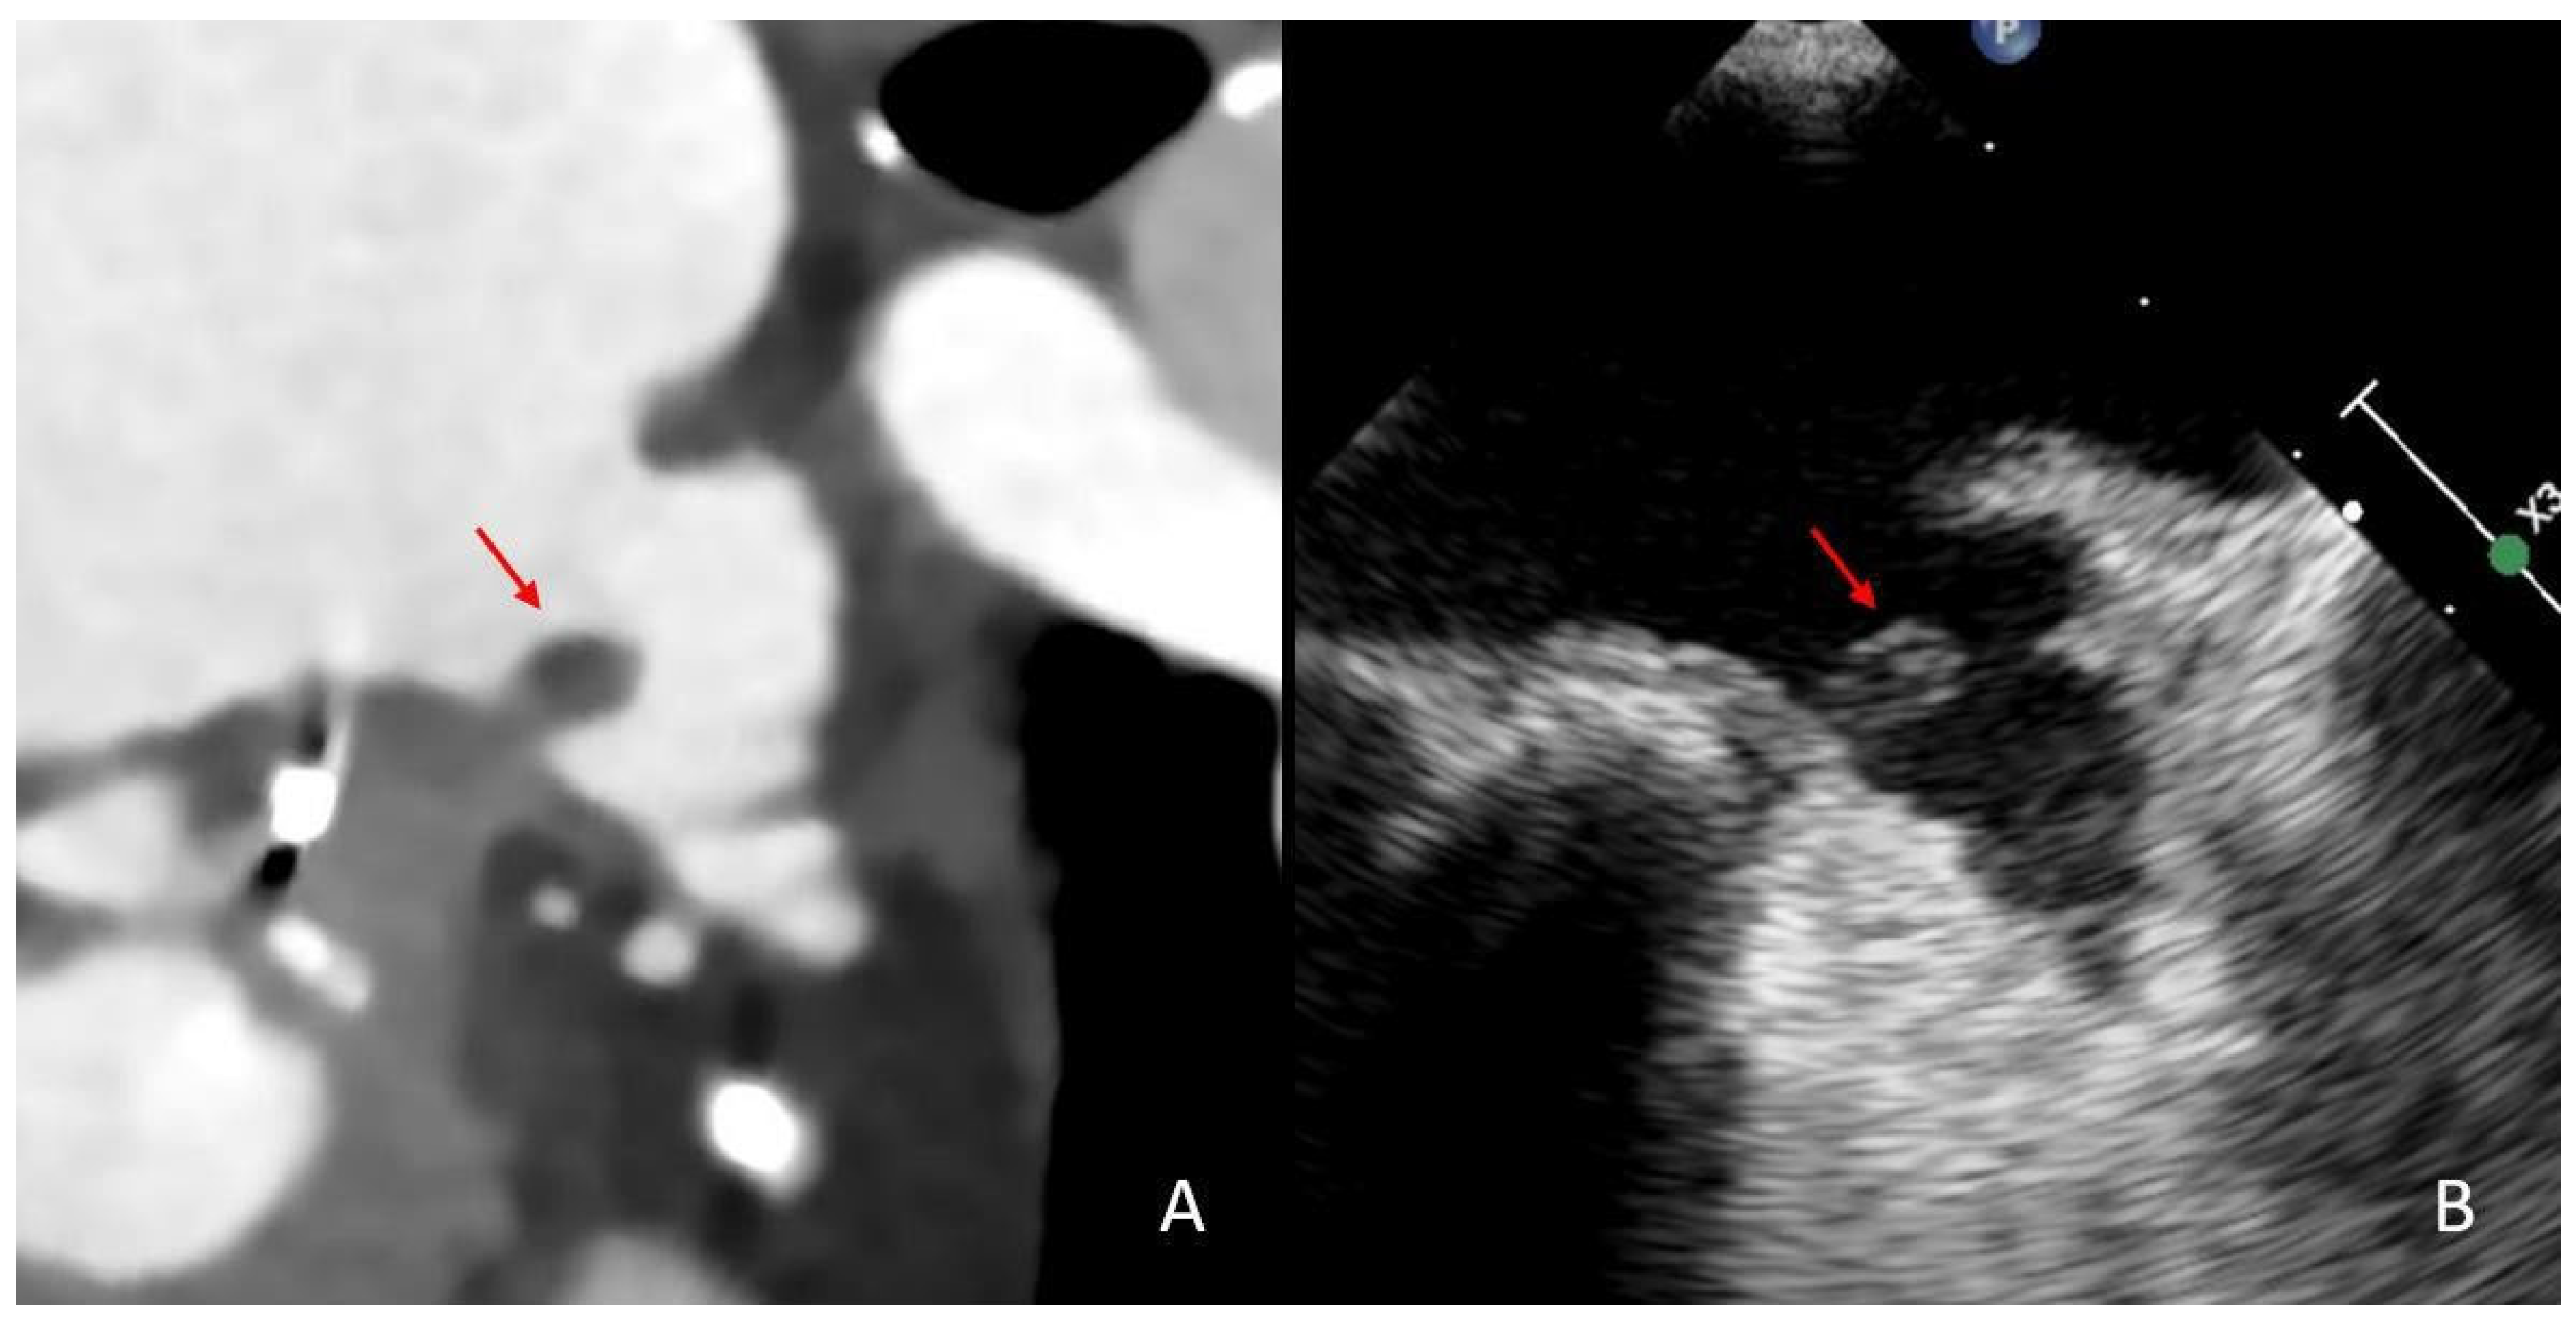

- Austein, F.; Eden, M.; Engel, J.; Lebenatus, A.; Larsen, N.; Both, M.; Piesch, T.C.; Salehi Ravesh, M.; Meyne, J.; Jansen, O.; et al. Practicability and Diagnostic Yield of One-Stop Stroke CT with Delayed-Phase Cardiac CT in Detecting Major Cardioembolic Sources of Acute Ischemic Stroke: A Proof of Concept Study. Clin. Neuroradiol. 2021, 31, 911–920. [Google Scholar] [CrossRef]

- Hur, J.; Kim, Y.J.; Lee, H.-J.; Ha, J.-W.; Heo, J.H.; Choi, E.-Y.; Shim, C.-Y.; Kim, T.H.; Nam, J.E.; Choe, K.O.; et al. Left atrial appendage thrombi in stroke patients: Detection with two-phase cardiac CT angiography versus transesophageal echocardiography. Radiology 2009, 251, 683–690. [Google Scholar] [CrossRef] [PubMed]

- Hur, J.; Kim, Y.J.; Lee, H.-J.; Nam, J.E.; Hong, Y.J.; Kim, H.Y.; Lee, J.W.; Choi, B.W. Cardioembolic stroke: Dual-energy cardiac CT for differentiation of left atrial appendage thrombus and circulatory stasis. Radiology 2012, 263, 688–695. [Google Scholar] [CrossRef] [PubMed]

- Barnea, R.; Agmon, I.N.; Shafir, G.; Peretz, S.; Mendel, R.; Naftali, J.; Shiyovich, A.; Kornowski, R.; Auriel, E.; Hamdan, A.; et al. Cardiac CT for intra-cardiac thrombus detection in embolic stroke of undetermined source (ESUS). Eur. Stroke J. 2022, 7, 212–220. [Google Scholar] [CrossRef]